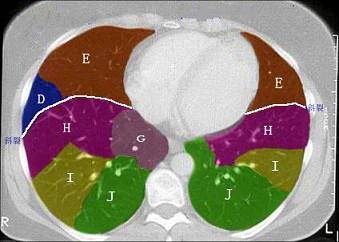

问题 结合肺段模式肺动脉干与右肺动脉层面肺动脉干与右肺动脉层面、心室层面、主动脉弓层面、 左右心房层面(如图),选出左肺上叶的组成 ( )

选项 A.A+B B.A+B+C C.A+B+C+D D.A+B+C+D+E E.A+B+C+D+E+F

答案 D